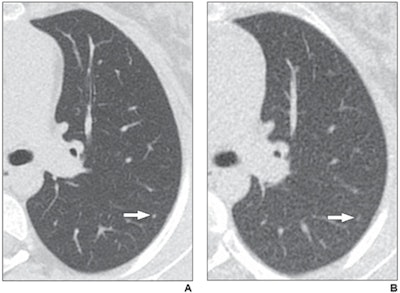

Axial reformatted clinical (1.083 mSv) and reduced dose (0.318 mSv) CT images from a 17-year-old girl with osteosarcoma. A 2-mm left lower lobe nodule is clearly visible in the left lower lobe on the clinical CT image (arrow in A). The same nodule is vaguely apparent on the reduced-dose CT image (arrow in B), classified as present but poorly visible. Images and caption courtesy of the American Journal of Roentgenology.

Axial reformatted clinical (1.083 mSv) and reduced dose (0.318 mSv) CT images from a 17-year-old girl with osteosarcoma. A 2-mm left lower lobe nodule is clearly visible in the left lower lobe on the clinical CT image (arrow in A). The same nodule is vaguely apparent on the reduced-dose CT image (arrow in B), classified as present but poorly visible. Images and caption courtesy of the American Journal of Roentgenology."CT performed at 0.3 mSv mean effective dose has acceptable diagnostic performance for lung nodule detection in children and young adults and has the potential to reduce patient dose or expand CT utilization (e.g., to replace radiography in screening or monitoring protocols)," the team concluded.